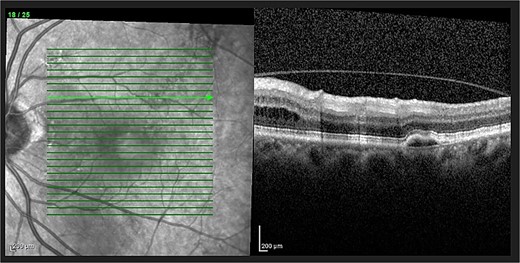

Optical coherence tomography (OCT) demonstrated an atrophied right macular. Whilst the left eye showed a thickened choroid, multiple pigment epithelial detachments (PED), subretinal fluid and intraretinal fluid nasally. This is shown in Figs 2 and 3.

OCT of left eye – showing IRF and pigment epithelial detachment.

The diagnosis of CSCR was made by the patient’s ophthalmologist, meeting diagnostic criteria as seen in Table 1. The patient meets major criteria with an OCT showing serous retinal detachment, and RPE alterations seen in Figs 2 and 3, respectively. Figure 2 displays a subfoveal choroidal thickness of 454 μm meeting the minor criteria.